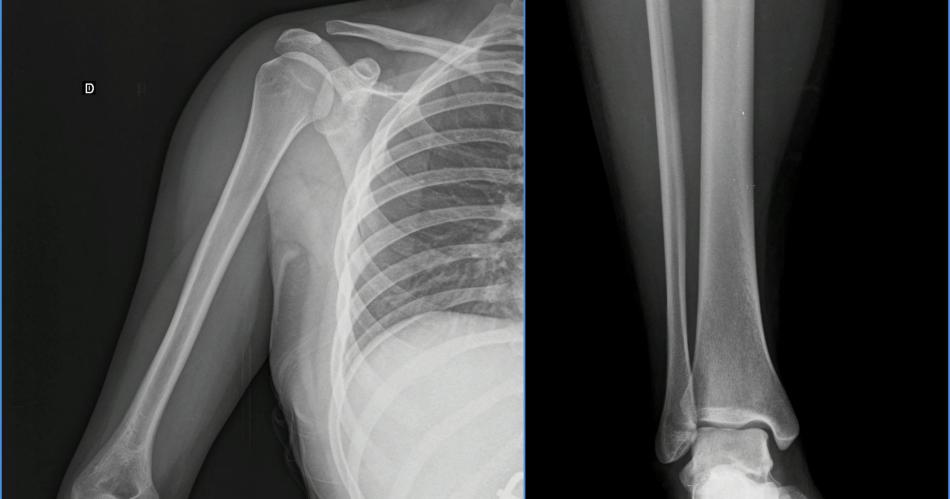

Los denunciados podrían ser imputados por "Lesiones graves", ya que por la fractura del hombro, el forense diagnosticó 45 días de curaciones.

Según la denunciante, uno de los jóvenes la manoseó y ante su reclamo y el de su novio, el acusado le propinó un golpe de puño al novio de la damnificada. Posteriormente, cuando eran expulsados del lugar por la Seguridad Privada, un amigo del primer acusado,la habría atacado a ella con puntapiés y le fracturó el hombro derecho, entre otras lesiones.

Ayer el médico forense examinó a la joven y diagnosticó 45 días de curaciones. La causa es investigada por la fiscal Silvia Jaime Luna.